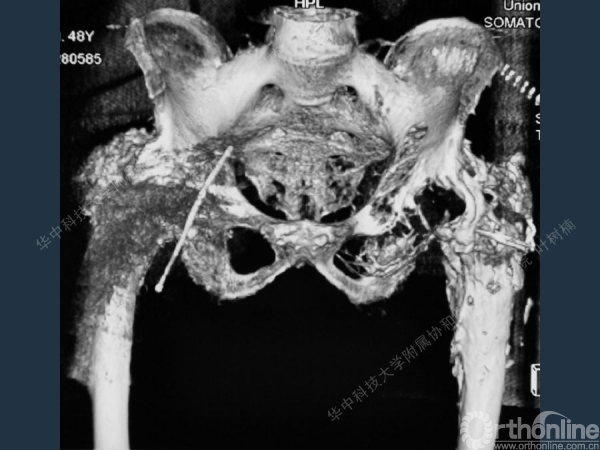

股骨侧翻修

髋臼缺损的处理